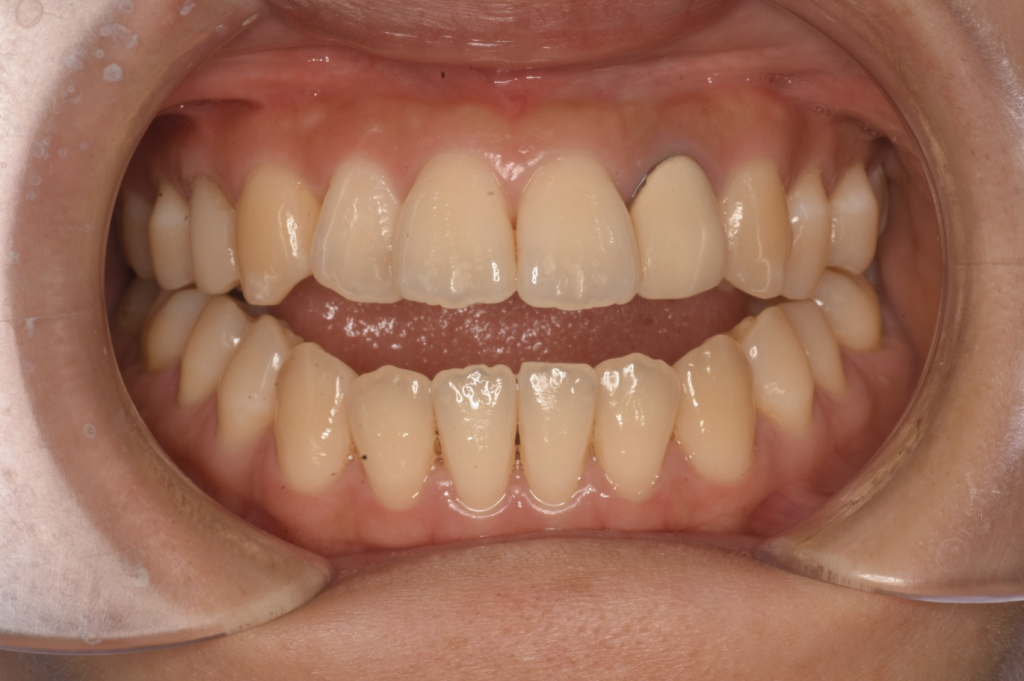

ほとんどの人が「開咬」と言うとき、それは前方の開咬を指します。前歯が開いている人は、上と下の前歯が外側に傾斜しているため、口を閉じたときに歯が接触しません。

開咬は不正咬合の一種で、顎を閉じたときに歯が正しく並んでいないことを意味します。